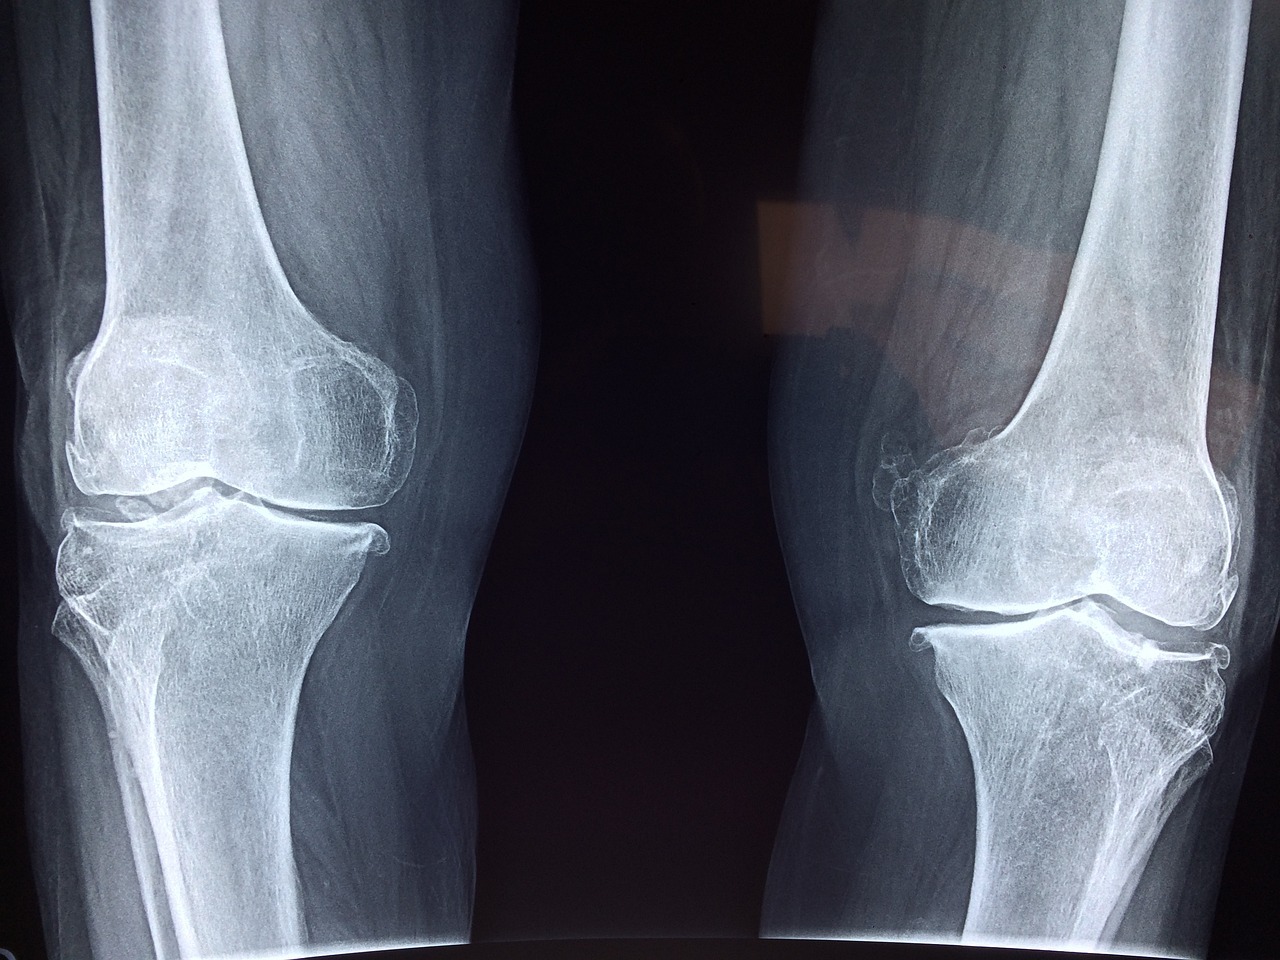

1. 뼈 건강 약화

비타민 D는 칼슘과 인이 흡수되는 것을 돕는 역할을 합니다. 결핍 시 뼈가 약해지며 골절의 위험이 증가합니다.